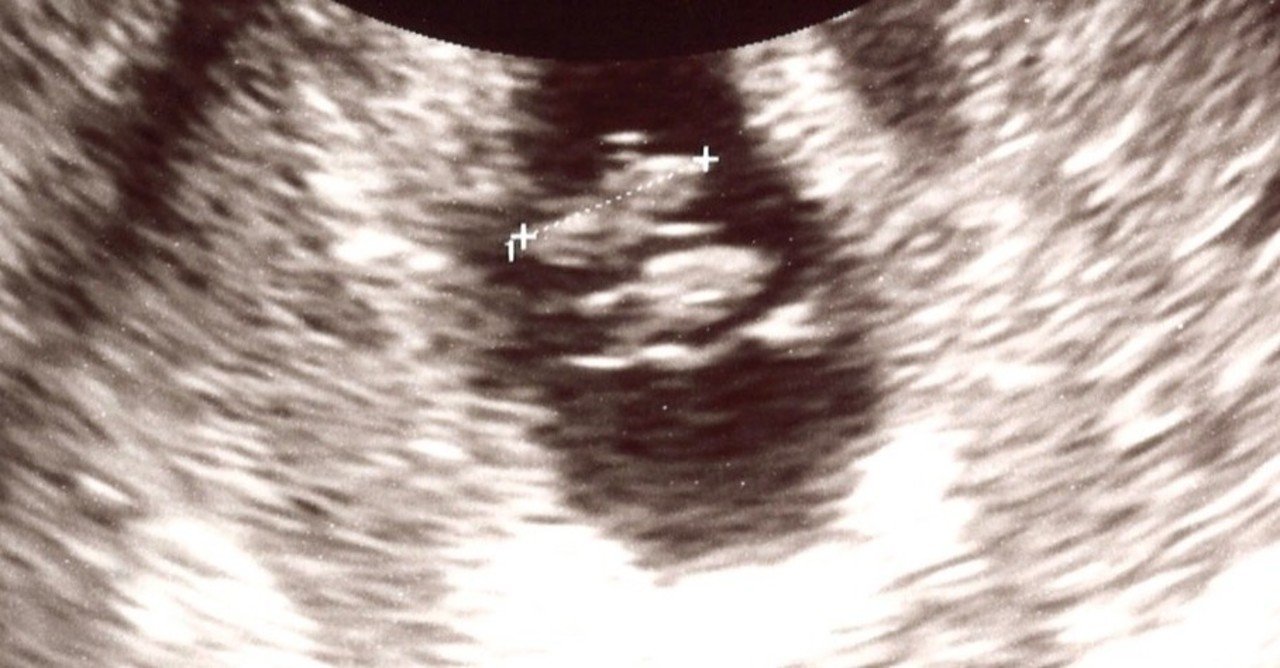

胎嚢のエコー写真について 妊娠初期 1ヶ月 2ヶ月 3ヶ月 4ヶ月 ベビカム相談室 ベビカム

妊娠3ヶ月 妊娠8週 9週 10週 11週 妊娠初期 の超音波写真 妊娠 出産 育児に関する総合情報サイト ベビカム

妊娠初期 10週 続ピカ待ち Md Twin Diary

妊娠10週目 エコー写真や胎児の大きさ 10週の壁 流産原因や症状 妊娠初期 All About

医師監修 妊娠10週のエコー写真を多数掲載 みんなのエピソードつき 年9月17日 ウーマンエキサイト 1 3